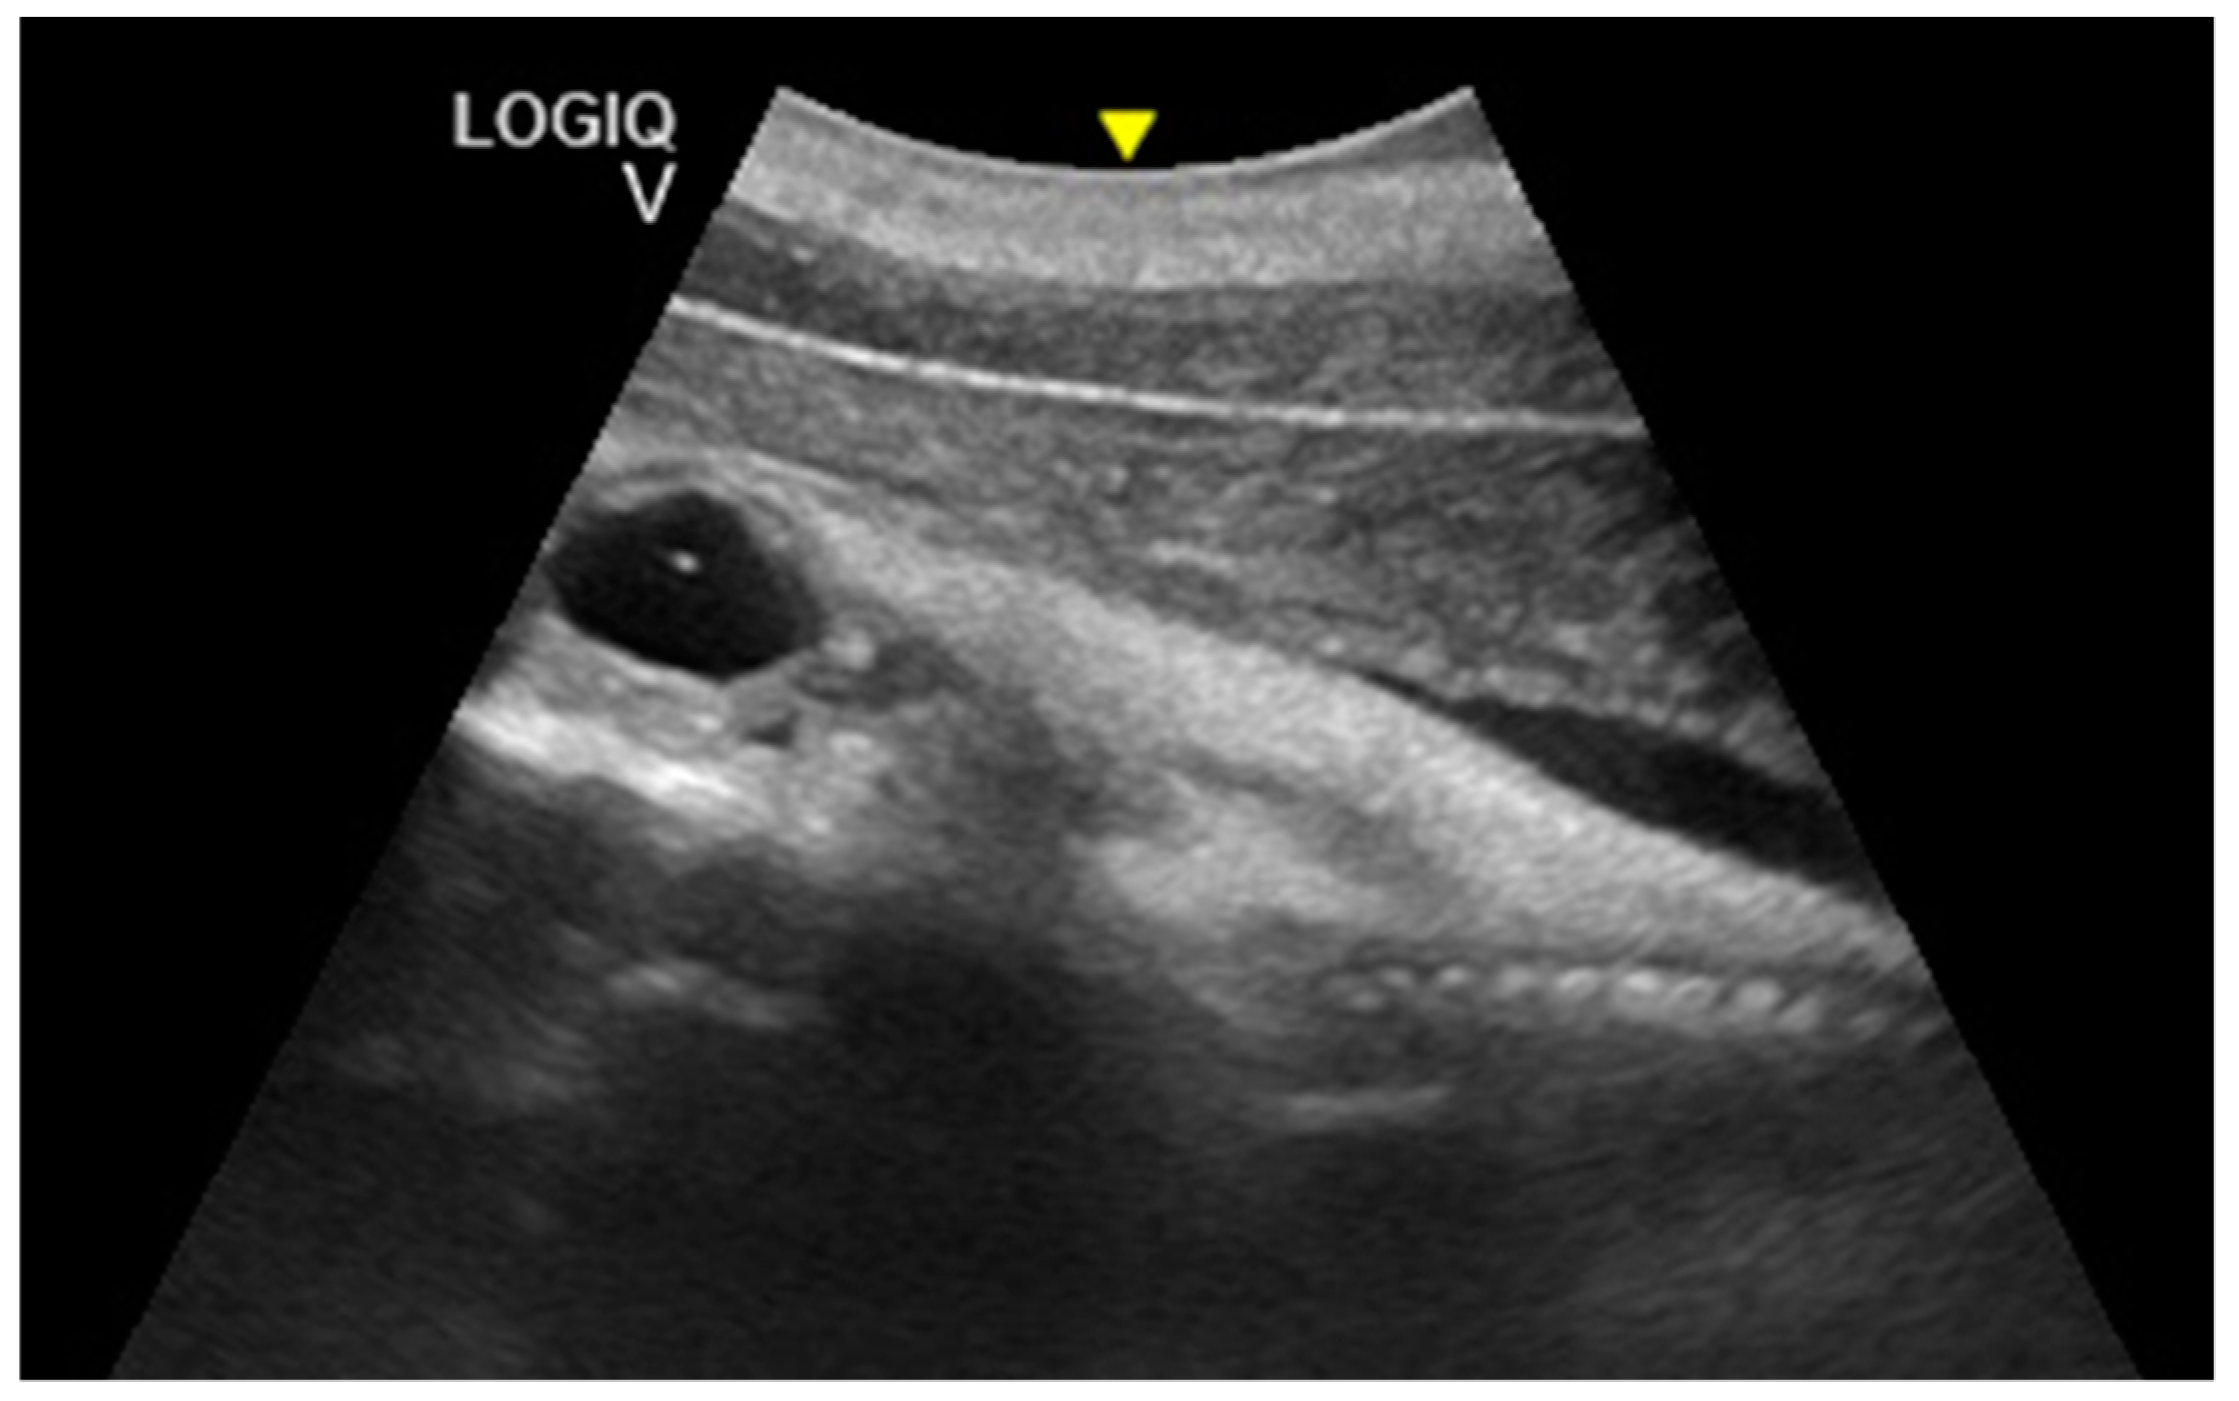

Pregnancy and Fetal Development: Cephalic Presentation and Other Descriptive Ultrasonographic Findings from Clinically Healthy Bottlenose Dolphins (Tursiops truncatus) under Human Care

3. Results